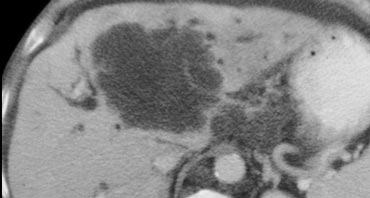

Cholangiocarcinoma usually presents as a mass of 5-20cm. In 65% there are satellite nodules and in some cases punctate calcifications are seen.

Cholangiocarcinoma: Non enhanced, arterial, portal venous and equilibrium phase. Cholangiocarcinoma: Non enhanced, arterial, portal venous and equilibrium phase.

First look at the images on the left and try to find good descriptive terms for what you see. Then continue.

The lesion on the left has the folowing characteristics:

• The lesion is hypodens in the arterial and portal venous phase with some peripheral enhancement.

• The lesion is hyperdense in the equilibrium phase indicating dens fibrous tissue.

• The lesion causes retraction of the liver capsule

The finding of an infiltrating mass with capsular retraction and delayed persistent enhancement is very typical for a cholangiocarcinoma.

Infiltrative cholangiocarcinoma does not cause mass effect, because when the stroma matures, the fibrous tissue will contract and cause retraction of the liver capsule.

There are not many tumors that cause retraction of the liver capsule, since most tumors will bulge.

The most common tumor that causes retraction besides cholangiocarcinoma is metastatic breast cancer.